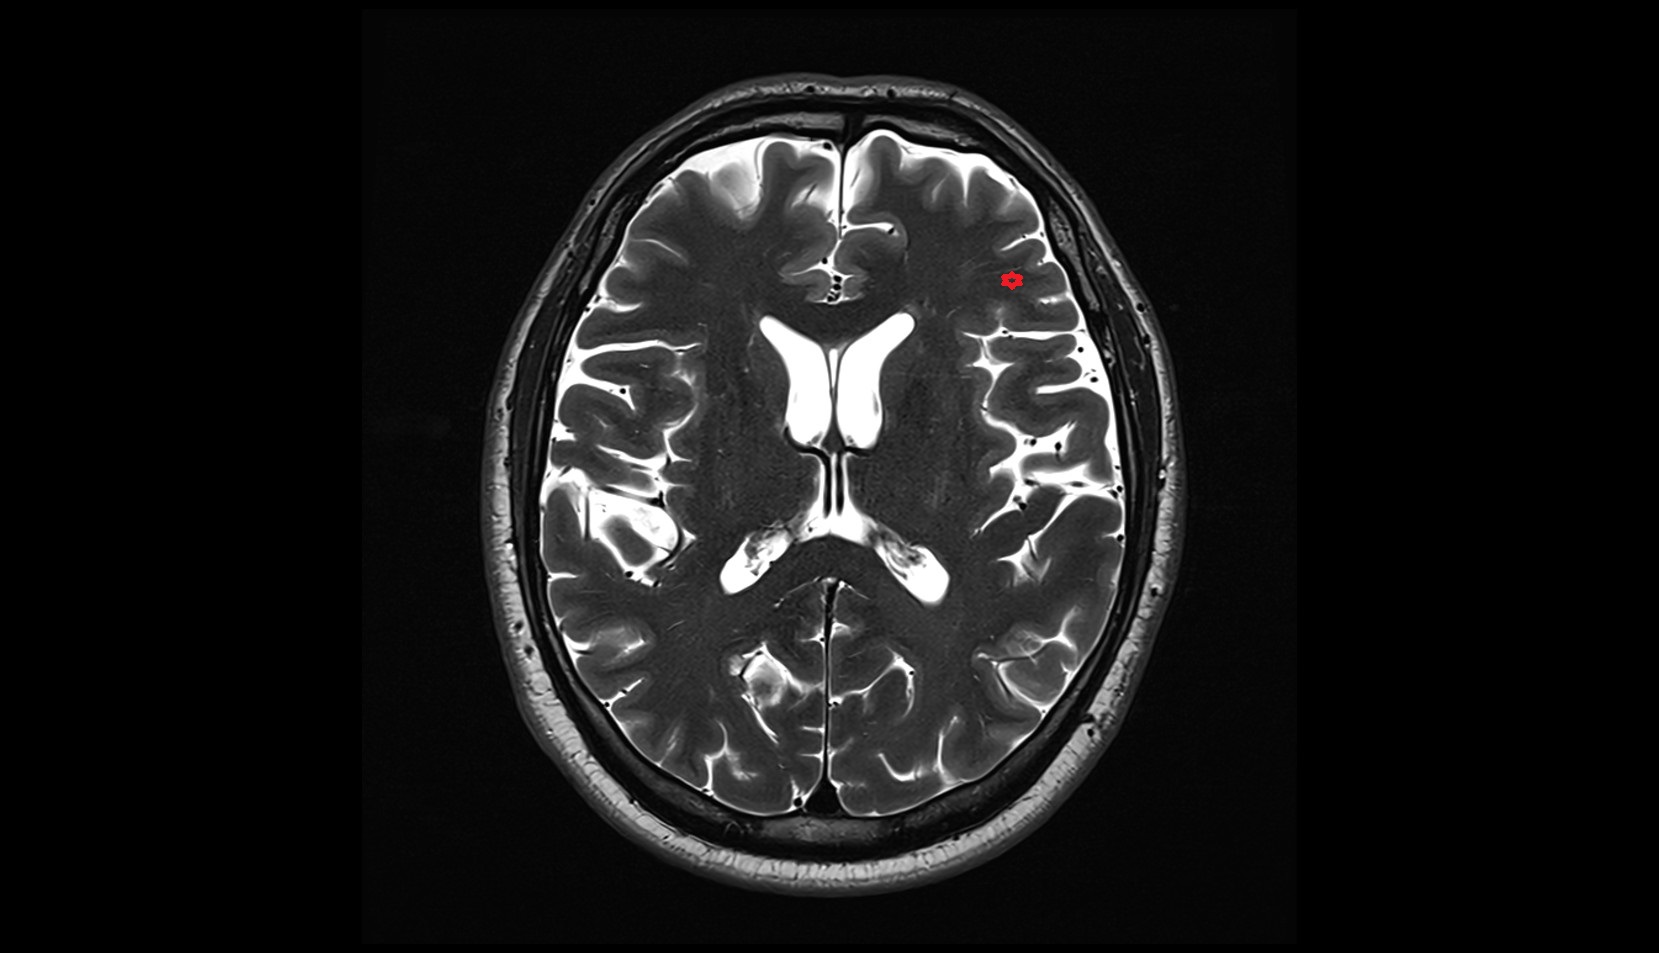

- Central sulcus